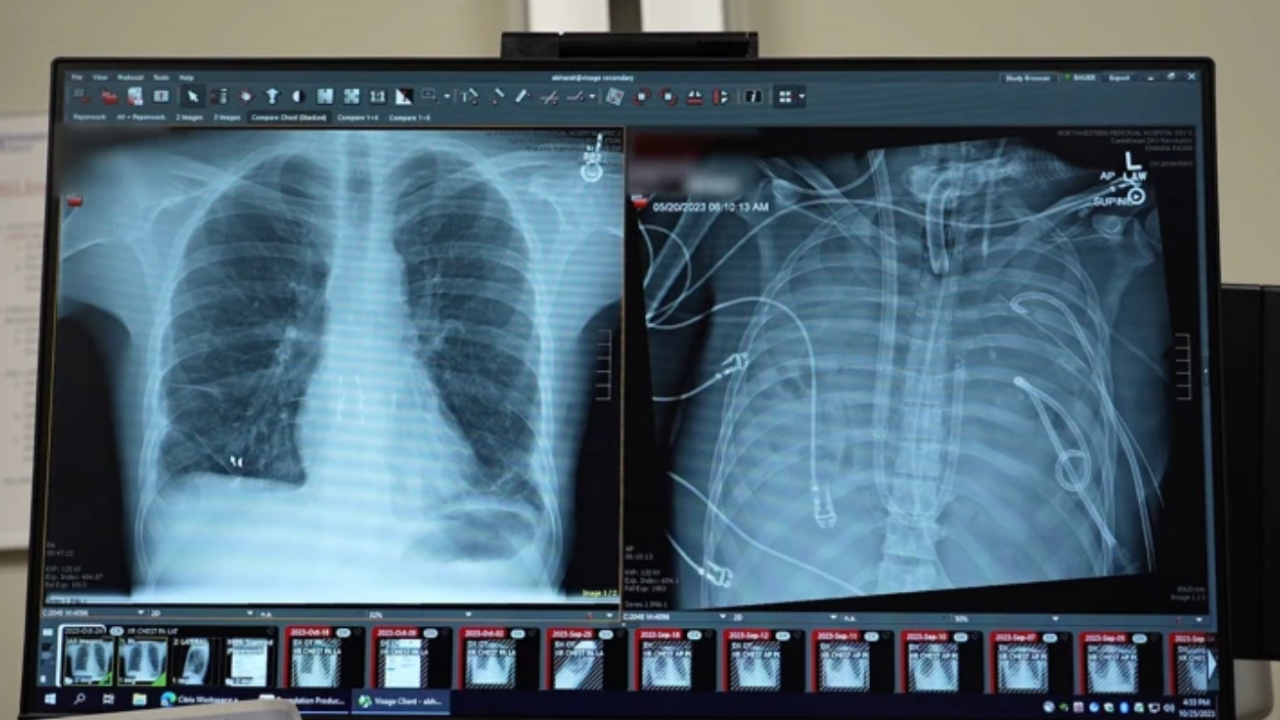

Northwestern Üniversitesi cerrahları, tıp literatürüne geçecek bir operasyonun detaylarını Med dergisinde yayımladı. Grip virüsüyle başlayan ve ardından ilaca dirençli bir bakteri enfeksiyonuna dönüşen vakada, 33 yaşındaki hastanın akciğerleri tamamen iflas etti. Akciğerleri irinle dolan ve septik şoka giren hasta, nakil yapılamayacak kadar kötü durumdaydı.

Hasta, hastaneye ulaştığında kalbi ve böbrekleri iflasın eşiğine gelmişti. Dr. Bharat, "Durumu o kadar ağırdı ki kalp durması yaşadı ve aktif olarak ölüyordu," diyerek durumun ciddiyetini vurguladı. Ekip, enfeksiyonun kaynağını kurutmak için radikal bir kararla akciğerleri çıkardı ve hastayı yapay sisteme bağladı.

Hasta, vücudunda akciğerleri olmadan geçirdiği 48 saatin ardından enfeksiyondan arındı ve vücudu nakil yapılabilecek kadar güçlendi. Bu süre zarfında uygun bağışçının bulunmasıyla başarılı bir çift taraflı akciğer nakli gerçekleştirildi.